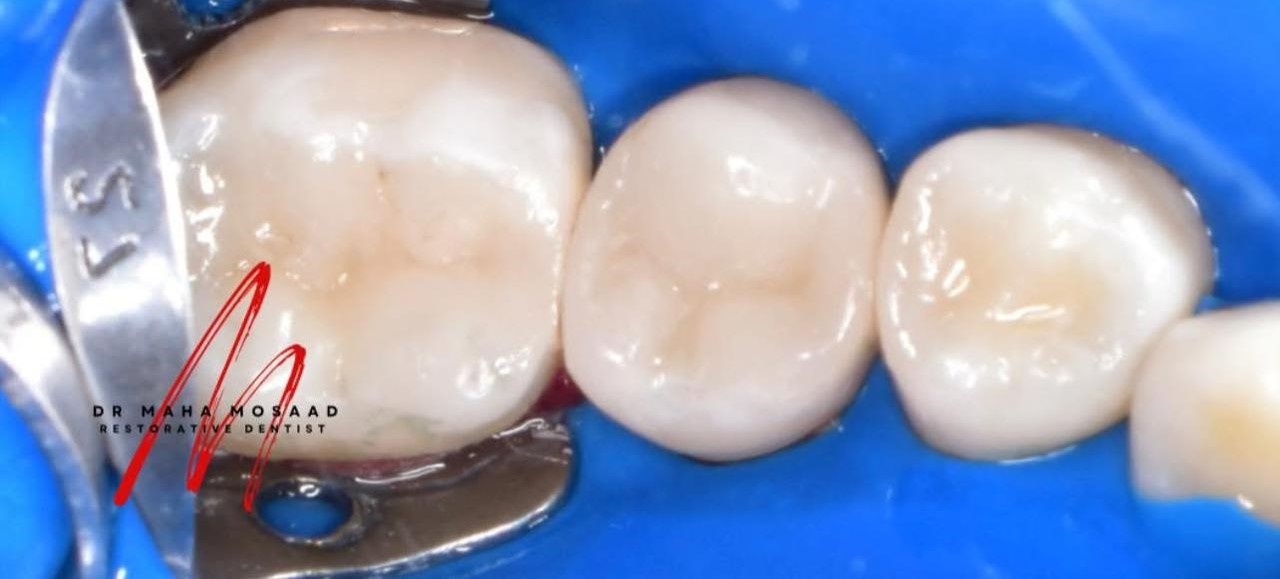

تجميل الضروس الخلفية و استعادة وظيفتها

استعادة وظيفة الضروس الخلفية و تجميلها